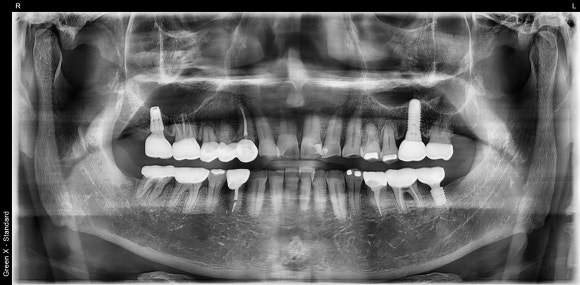

20250217

최종 파노라마 사진입니다.

- 워랜텍 임플란트를 사용했습니다. 출시 이후로 거의 변하지 않은 안정적인 디자인, 믿음직스러운 임상결과로 저는 워랜텍을 선호합니다.